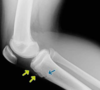

Qué fracura antebrazo se observa?

Monteggia Fx cúbito proximal + luxación radio prox ( n. interoseo posterior ) la Cabra tira al MONTE